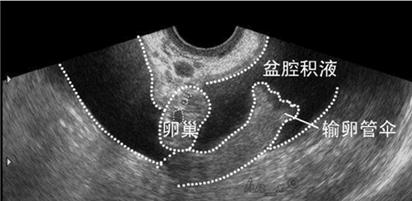

很多女性拿到检查报告,看到上面的盆腔积液就惊慌失措了。盆腔积液究竟是什么呢?

在解剖上,盆腔处于腹腔最低的部位,因此当盆腹腔内脏器有渗出液、漏出液或出血时,液体首先积聚在盆腔,从而形成盆腔积液。所以呢,盆腔积液是一种临床表现,而不是一种疾病名称,确切地说这仅是影像学对盆腔内液体的一种描述。虽然有时存在盆腔炎会伴发盆腔积液,但有盆腔积液不一定是有盆腔炎。

每个女性的一个月经周期中,有两个时间段可能会出现生理性盆腔积液,一是每月排卵后,卵泡液、输卵管液可以短暂积聚于盆腔;二是经期以后,宫腔里的部分经血倒流至盆腔内,或近期盆腔内腹膜充血渗出等。所以女性朋友经常发现在经期或排卵期容易出现盆腔积液,这属于生理现象。超声检查积液深度一般在1~2cm,通常无明显症状,无需特殊处理,不用太紧张。